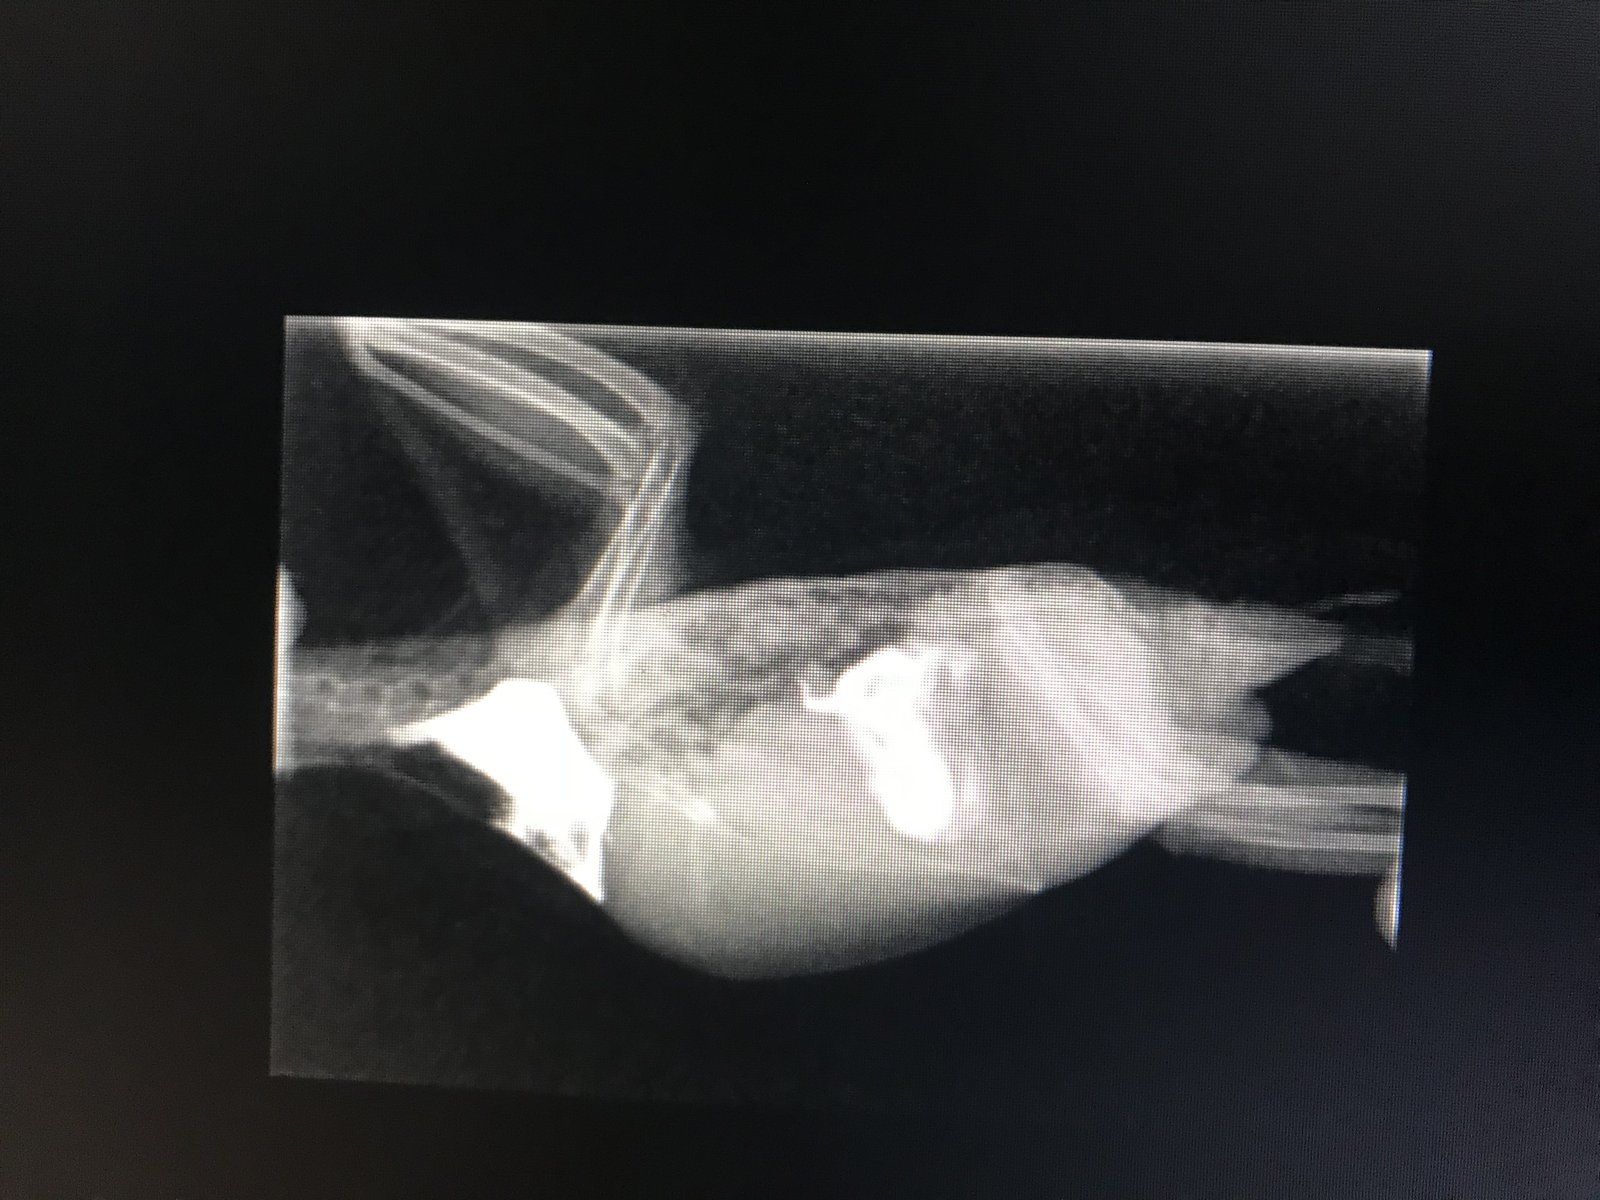

Wkki Опубликовано 9 января, 2020 Автор #20 Опубликовано 9 января, 2020 1 час назад, Linka сказал: ?а жидкость нельзя откачать? Это из за удара эта жидкость образовалась? Честно говоря не знаю говорчт что да из за удара так как нет диафрагмы, защиты будут давать антибиотик и брать анализ крови на кровотечение он в реанимации, критичны эти сутки но они говорят что вряд ли он выживет ??? на снимке все легкие белые что не есть норма

Wkki Опубликовано 10 января, 2020 Автор #31 Опубликовано 10 января, 2020 Только что позвонили с повторного контрастного рентгена... дела плохи все органы сдавлены массой: это может быть жидкость, неоплазия или вирус. Попросила выслать снимки. Любые предложения будут рассмотрены в лечение. Завтра в 11 буду там, нужно принять решение....

Wkki Опубликовано 11 января, 2020 Автор #32 Опубликовано 11 января, 2020 Сделали ему третий рентген всеоа было подозрение на гранулёму и абсцесс то сегодня вроде как с кишечником что то типо из за удара его раздуло их понять сложно так как диагноза точного нет но они смотрят динамику если эта масса будет уменьшатся его будут оперировать из хороших новостей- дышит лучше и пытался махать крыльями. Сам не ест. Я выложу ОАК и рентгены в порядке очереди если у кого-то любые предложения есть все будет рассмотрено!

Delfin Опубликовано 11 января, 2020 #34 Опубликовано 11 января, 2020 вон то бело -я так понимаю это барий или типа того (конрастное вещество)

Wkki Опубликовано 11 января, 2020 Автор #35 Опубликовано 11 января, 2020 1 час назад, Delfin сказал: вон то бело -я так понимаю это барий или типа того (конрастное вещество) Без понятия внизу живота непонятная масса сдавливает внутренние органы это то что их больше всего сейчас обеспокоило будут делать повторный рентген завтра что б смотреть динамику он не какает в норме. Не часто как я поняла. Они хотят посмотреть как проходит пища. Плюс что-то дают для стимуляции желудка прогнозы плохие.